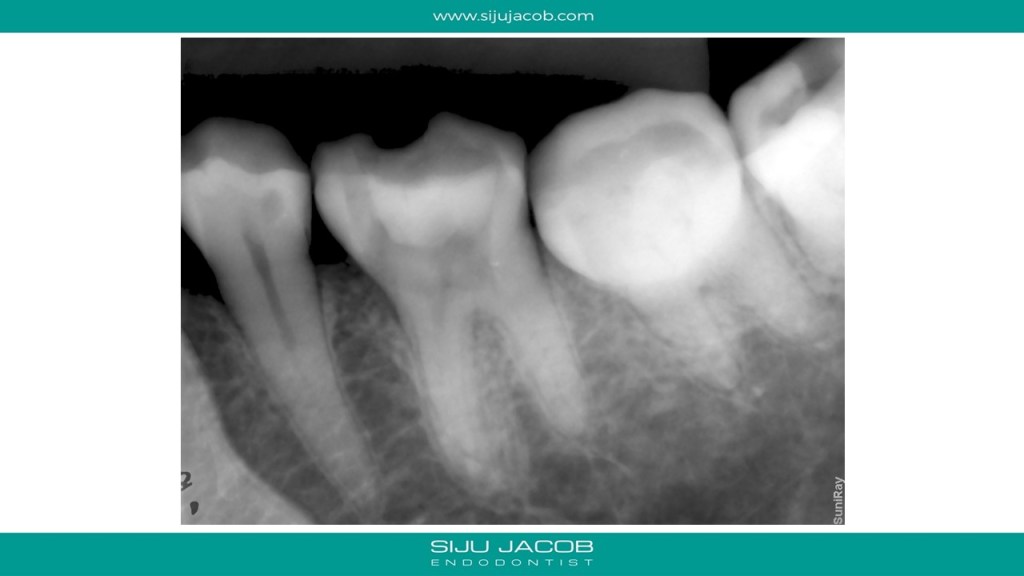

This mandibular molar was previously accessed by an endodontist and then referred. There was a perforation mesially and the canals were located in strange positions. To add to that, the canals were very hard to negotiate and the “feel” was very different to conventional canals. The dentine felt harder than usual. I didn’t want to risk using rotary niti in this case because the feel to rotary too was different when i tried. So, I hand-filed all the canals. Skinny preps in the canal and MTA to seal the Perforation.